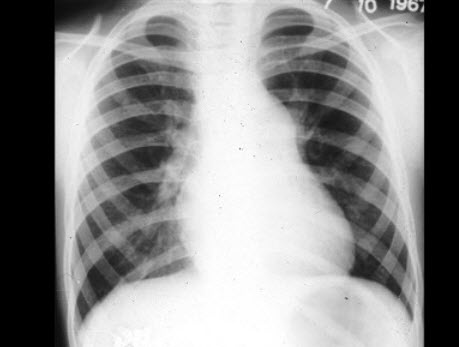

男孩,8岁。体检时发现胸骨左缘第2肋间有粗糙喷射性全收缩期杂音,向颈部传导,肺动脉瓣区第2音减弱。经右心导管检查,证实为中度肺动脉瓣狭窄。进行X线检查,如图所示,下列哪一项不是特点()